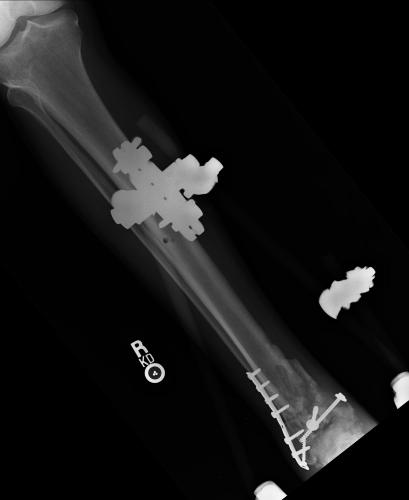

Pre-corrective surgery X-Rays of the damaged right & left legs / ankles

These x-rays were taken at Dr Armendariz’s office, just prior to performing any corrective surgery. As can be seen in these images,

there was no tibia bracing provided by Dr. Keller. Liam was released from Dr Keller’s care with instructions that full weight bearing could

be accomplished within 2 months of Keller’s last surgical procedure. The best example to examine is the second image (from the left) of the

top how. Notice how the bones that should be aligned with the tibia are in fact on the other side of the leg. The third image shows how badly

Liam’s left foot was twisted as a result of the pool placement of the external fixation. What is not obvious is that the screw at the bottom

of the plate on the right fibula missed being screwed into the plate.